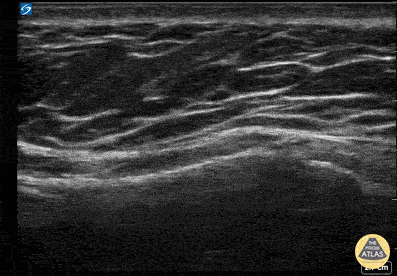

Sternum Fracture 50 y/o female patient who was involved in a recent, low energy RTC as a driver. She attends the ED by her means, stable and able to walk, complaining of central chest pain, which worsens when lying flat. There is no SOB, O2Sat is normal, Lung examination is unremarkable, and Lung POCUS shows no abnormalities. A POCUS scan of the sternum was performed: Identify the skin, fatty and soft tissues from top to bottom. Notice the acoustic shadow (black) deep to the anterior wall of the sternum. Sliding the probe from the sternal manubrium down towards the sternal body, notice the lower echogenicity at the level of the sternal angle. Also, see how the anterior bone cortex is interrupted at the body level, featuring a clear gap located at the centre of the screen at the end of this clip. Dr Felipe Urriola P. Resuscitation Fellow - Emergency Medicine. The Royal London Hospital, Barts Health NHS Trust, London.